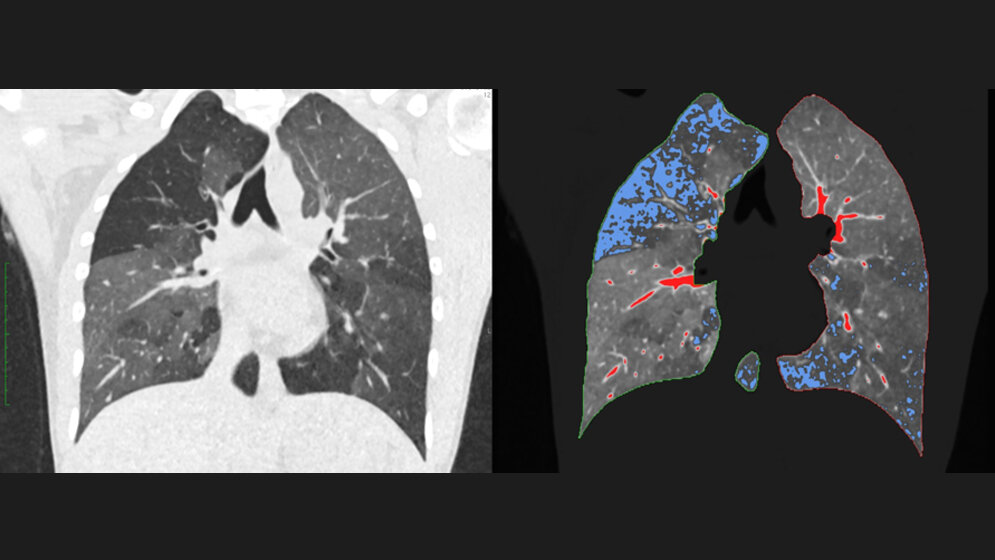

Mit den umfangreichen Datensätzen moderner CT-Geräte lassen sich in Zeiten, in denen Computerkapazitäten kaum ein Problem mehr darstellen, aber auch ganz andere Auswertungen machen. Ein Beispiel ist die quantitative Computertomographie (qCT). „Bei diesem Verfahren wertet die Software nicht nur durchschnittliche Dichtewerte aus, sondern analysiert jeden einzelnen dreidimensionalen Pixel oder ‚Voxel‘ separat und setzt sie miteinander in Verbindung“, erläutert Gawlitza.

In einem Organ wie der Lunge kann das hoch interessant sein: Dort wertet die qCT pro Lungenflügel mehr als zwei Millionen Voxel aus. Bei Patienten mit einer chronisch-obstruktiven Lungenerkrankung (COPD) zum Beispiel ist die Lunge nicht homogen belüftet. Es gibt vielmehr Areale, in denen die Luft beim Ausatmen „steckenbleibt“ und andere, die weitgehend normal arbeiten. „Solche schlecht belüfteten Areale können wir mit der qCT erkennen“, so Gawlitza. Ein anderes Beispiel sind Verkalkungen der Herzkranzgefäße, die in der normalen CT ohne Quantifizierung lediglich als dichte Ablagerungen erscheinen. In der qCT dagegen kann der Aufbau der Kalk-Plaques sowie deren Volumen detailliert dargestellt und vor allem quantifiziert werden. Insbesondere für die individuelle Risikoabschätzung des Patienten ist dies relevant.

Konkret haben die Mannheimer mehrere qCT-Parameter – darunter Lungenvolumen, mittlere Lungendichte und den Anteil der schlecht belüfteten Lungenareale – in ein neuronales Netzwerk gefüttert. Zum Einsatz kam das dafür in Mannheim eigens für die qCT-Auswertung der Lunge entwickelte Programm PrediCT. „Letztlich rechnet die Software die Lungenfunktion auf Basis unterschiedlicher Modelle durch und bildet einen Mittelwert. Den haben wir dann mit dem Goldstandard, einer Messung der Lungenfunktion mittels Bodyplethysmographie, verglichen“, so Gawlitza.